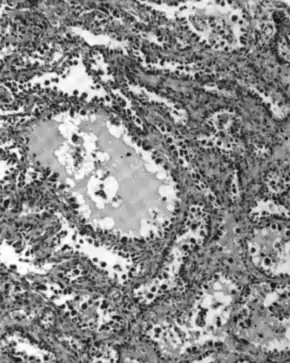

Micrograph of serous carcinoma, a type of ovarian cancer, diagnosed in peritoneal fluid

Most people with epithelial ovarian carcinoma, about two-thirds, have a serous carcinoma,[21] though this proportion is estimated as high as 80%.[24][49] Low-grade serous carcinoma is less aggressive than high-grade serous carcinomas, though it does not typically respond well to chemotherapy or hormonal treatments.[21] Serous carcinomas are thought to begin in the Fallopian tube.[48] Histologically, serous adenocarcinomas have psammoma bodies. Low-grade serous adenocarcinomas resemble Fallopian tube epithelium, whereas high-grade serous adenocarcinomas show anaplasia and nuclear atypia.[22]